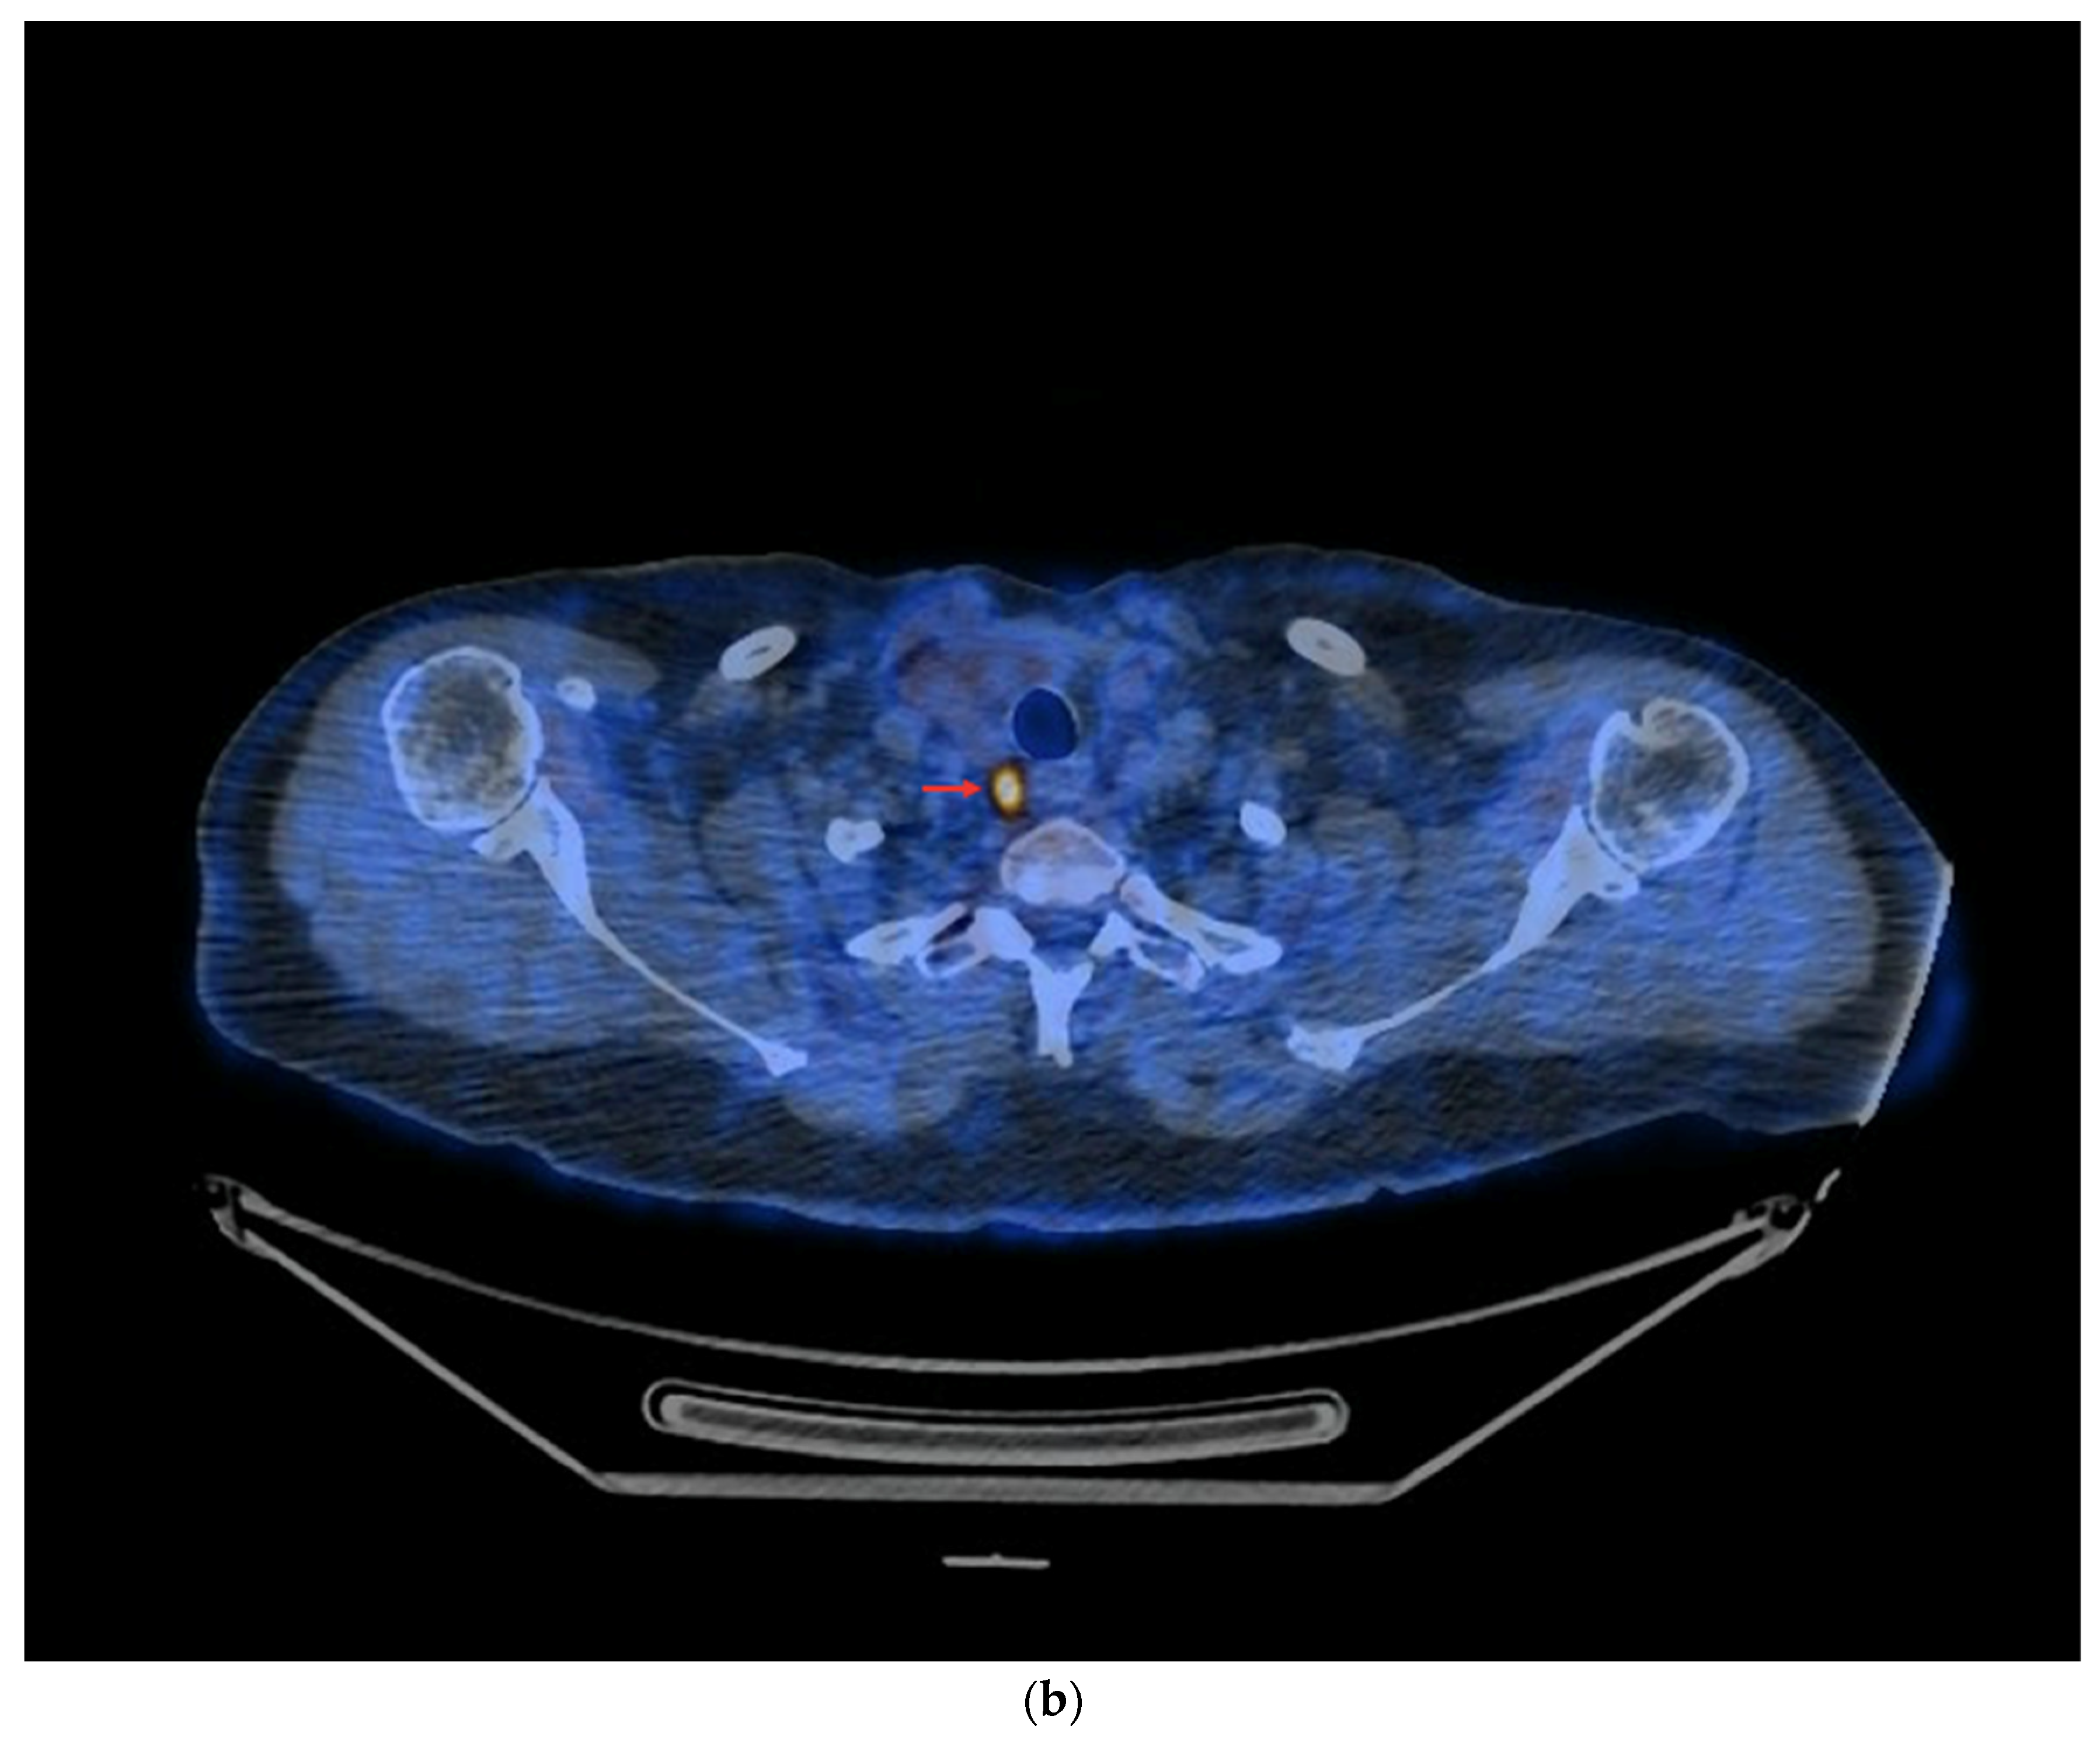

Among the 73 PET/CT examinations with [18F]FDG, 25 examinations were performed without rhTSH stimulation and 48 were performed with rhTSH stimulation. In the subgroup of 25 PET/CT examinations without rhTSH stimulation, in 10 (10/25—40%), positive results of the PET/CT were obtained (Figure 7a,b). The other 15 studies in this subgroup (15/25—60%) were assessed as negative, and no foci of increased [18F]FDG accumulation associated with DTC were found.

Figure 7.

PET/CT with [18F]FDG without rhTSH stimulation (a) Maximum-intensity projection (MIP). An example of accumulation of the [18F]FDG in the lymph nodes: left cervical and right mediastinal (red arrows). (b) Axial fusion projection. An example of accumulation of the [18F]FDG in the right mediastinal lymph node (red arrow).